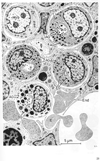

骨髄【こつずい】(骨髄は骨の内部、すなわち長骨の髄腔や骨端およびその他の骨の海綿骨の小柱骨の間を満たす組織で、血球を産生する造血組織である。発育期にある幼小児の骨髄はすべて赤色骨髄で占められているが、成長ともに長骨の骨髄には黄色骨髄が次第に増加する。7歳以後、黄色骨髄は上肢の長骨の遠位側から近位側に向かって次第に増加し、成人では、赤色骨髄は主として体幹の骨(頭蓋骨・椎骨・胸骨・肋骨)および上肢帯・下肢帯の骨(寛骨など)と上肢・下肢では上腕骨・大腿骨の海綿質の近位端に限られる。骨髄は骨髄腔および海綿質を満たす軟らかい組織で血球をつくる大切な場所である。胎生期や乳児期にはほとんどすべてが赤色骨髄であるが、成長とともに黄色骨髄におきかわり、成人では半量に達する。赤色骨髄は造血(血球新生)が行われる場所であるが、黄色骨髄は赤色骨髄が脂肪化して造血能力を失ったものである。さらに年をとると、黄色骨髄の脂肪組織は変性、萎縮し、骨髄はゼラチン様になる。これを膠様骨髄という。また、結合組織繊維におきかわったものを線維骨髄という。骨の栄養孔から入った動脈は何回も枝分かれし赤色骨髄のなかで洞様毛細血管(sinusoid capillary)となる。この血管は内腔が広いこと、内皮を血球が通りぬけること、内皮細胞に食作用の能力(phagocytic activity)があることを特徴とする。洞様毛細血管の外は造血組織になっており、ここでつくられた血球のうち、完成した血球だけが内皮をくぐりぬけ血管内にでるが、そのメカニズムはよくわかっていない。洞様毛細血管は集まって中心静脈となり栄養孔から外へ出る。造血組織は細網細胞と細網線維の網からなる細網組織であり、その網眼を数多くの種々の段階の造血細胞が満たしているのである。骨髄とは血液疾患の診断に際してきわめて大切で、骨髄穿刺によって骨髄をとりだして観察することが行われている。胸骨穿刺が最もよく用いられる。骨髄は骨の本質的構成要素ではない。骨髄のない骨は小型動物(ことに魚類)には至る所にみられ、造血は脾臓や肝臓で行われる。また人体でも、耳小骨のような小骨や鼻腔壁の薄い骨片は骨髄を欠いている。大きな骨でも、頭蓋骨では骨髄の代わりに空気をいれているものがある(含気骨)。これは骨格を軽くするためと考えられ、鳥類では体幹にも含気骨がよく発達している。赤色骨髄は造血組織が仮に骨の中の空間を利用して占拠しているのに過ぎないのである。)